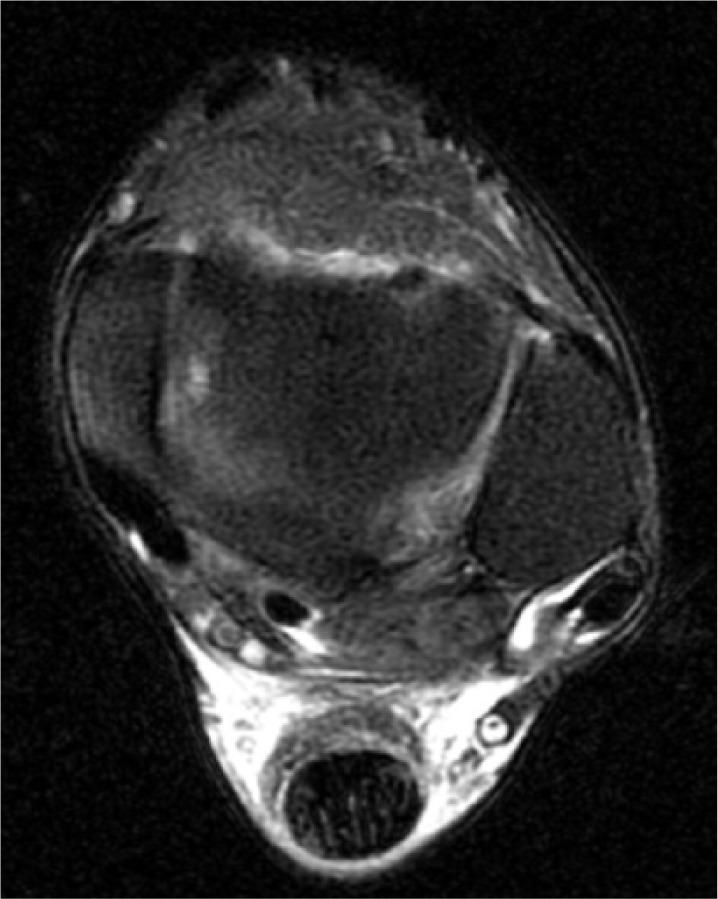

We reviewed and analysed this patient's records containing the sport-specific anamnesis, pre-existing condition, anamnesis of medications and therapy. The three injuries were magnetic resonance imaging-proven. Furthermore, the tendon's condition was examined histologically in the context of the operative treatment through lace technique of the Achilles tendon and transfer of the peroneus brevis to the peroneus longus. We also researched the literature for bilateral ruptures of the peroneal tendons.

我们回顾并分析了该患者的记录,包括运动专项病史、既往病史、用药史和治疗情况。这三处损伤均经磁共振成像证实。此外,在通过跟腱编织技术和将腓骨短肌转移至腓骨长肌进行手术治疗的过程中,对肌腱状况进行了组织学检查。我们还在文献中搜索了腓骨肌腱双侧断裂的病例。